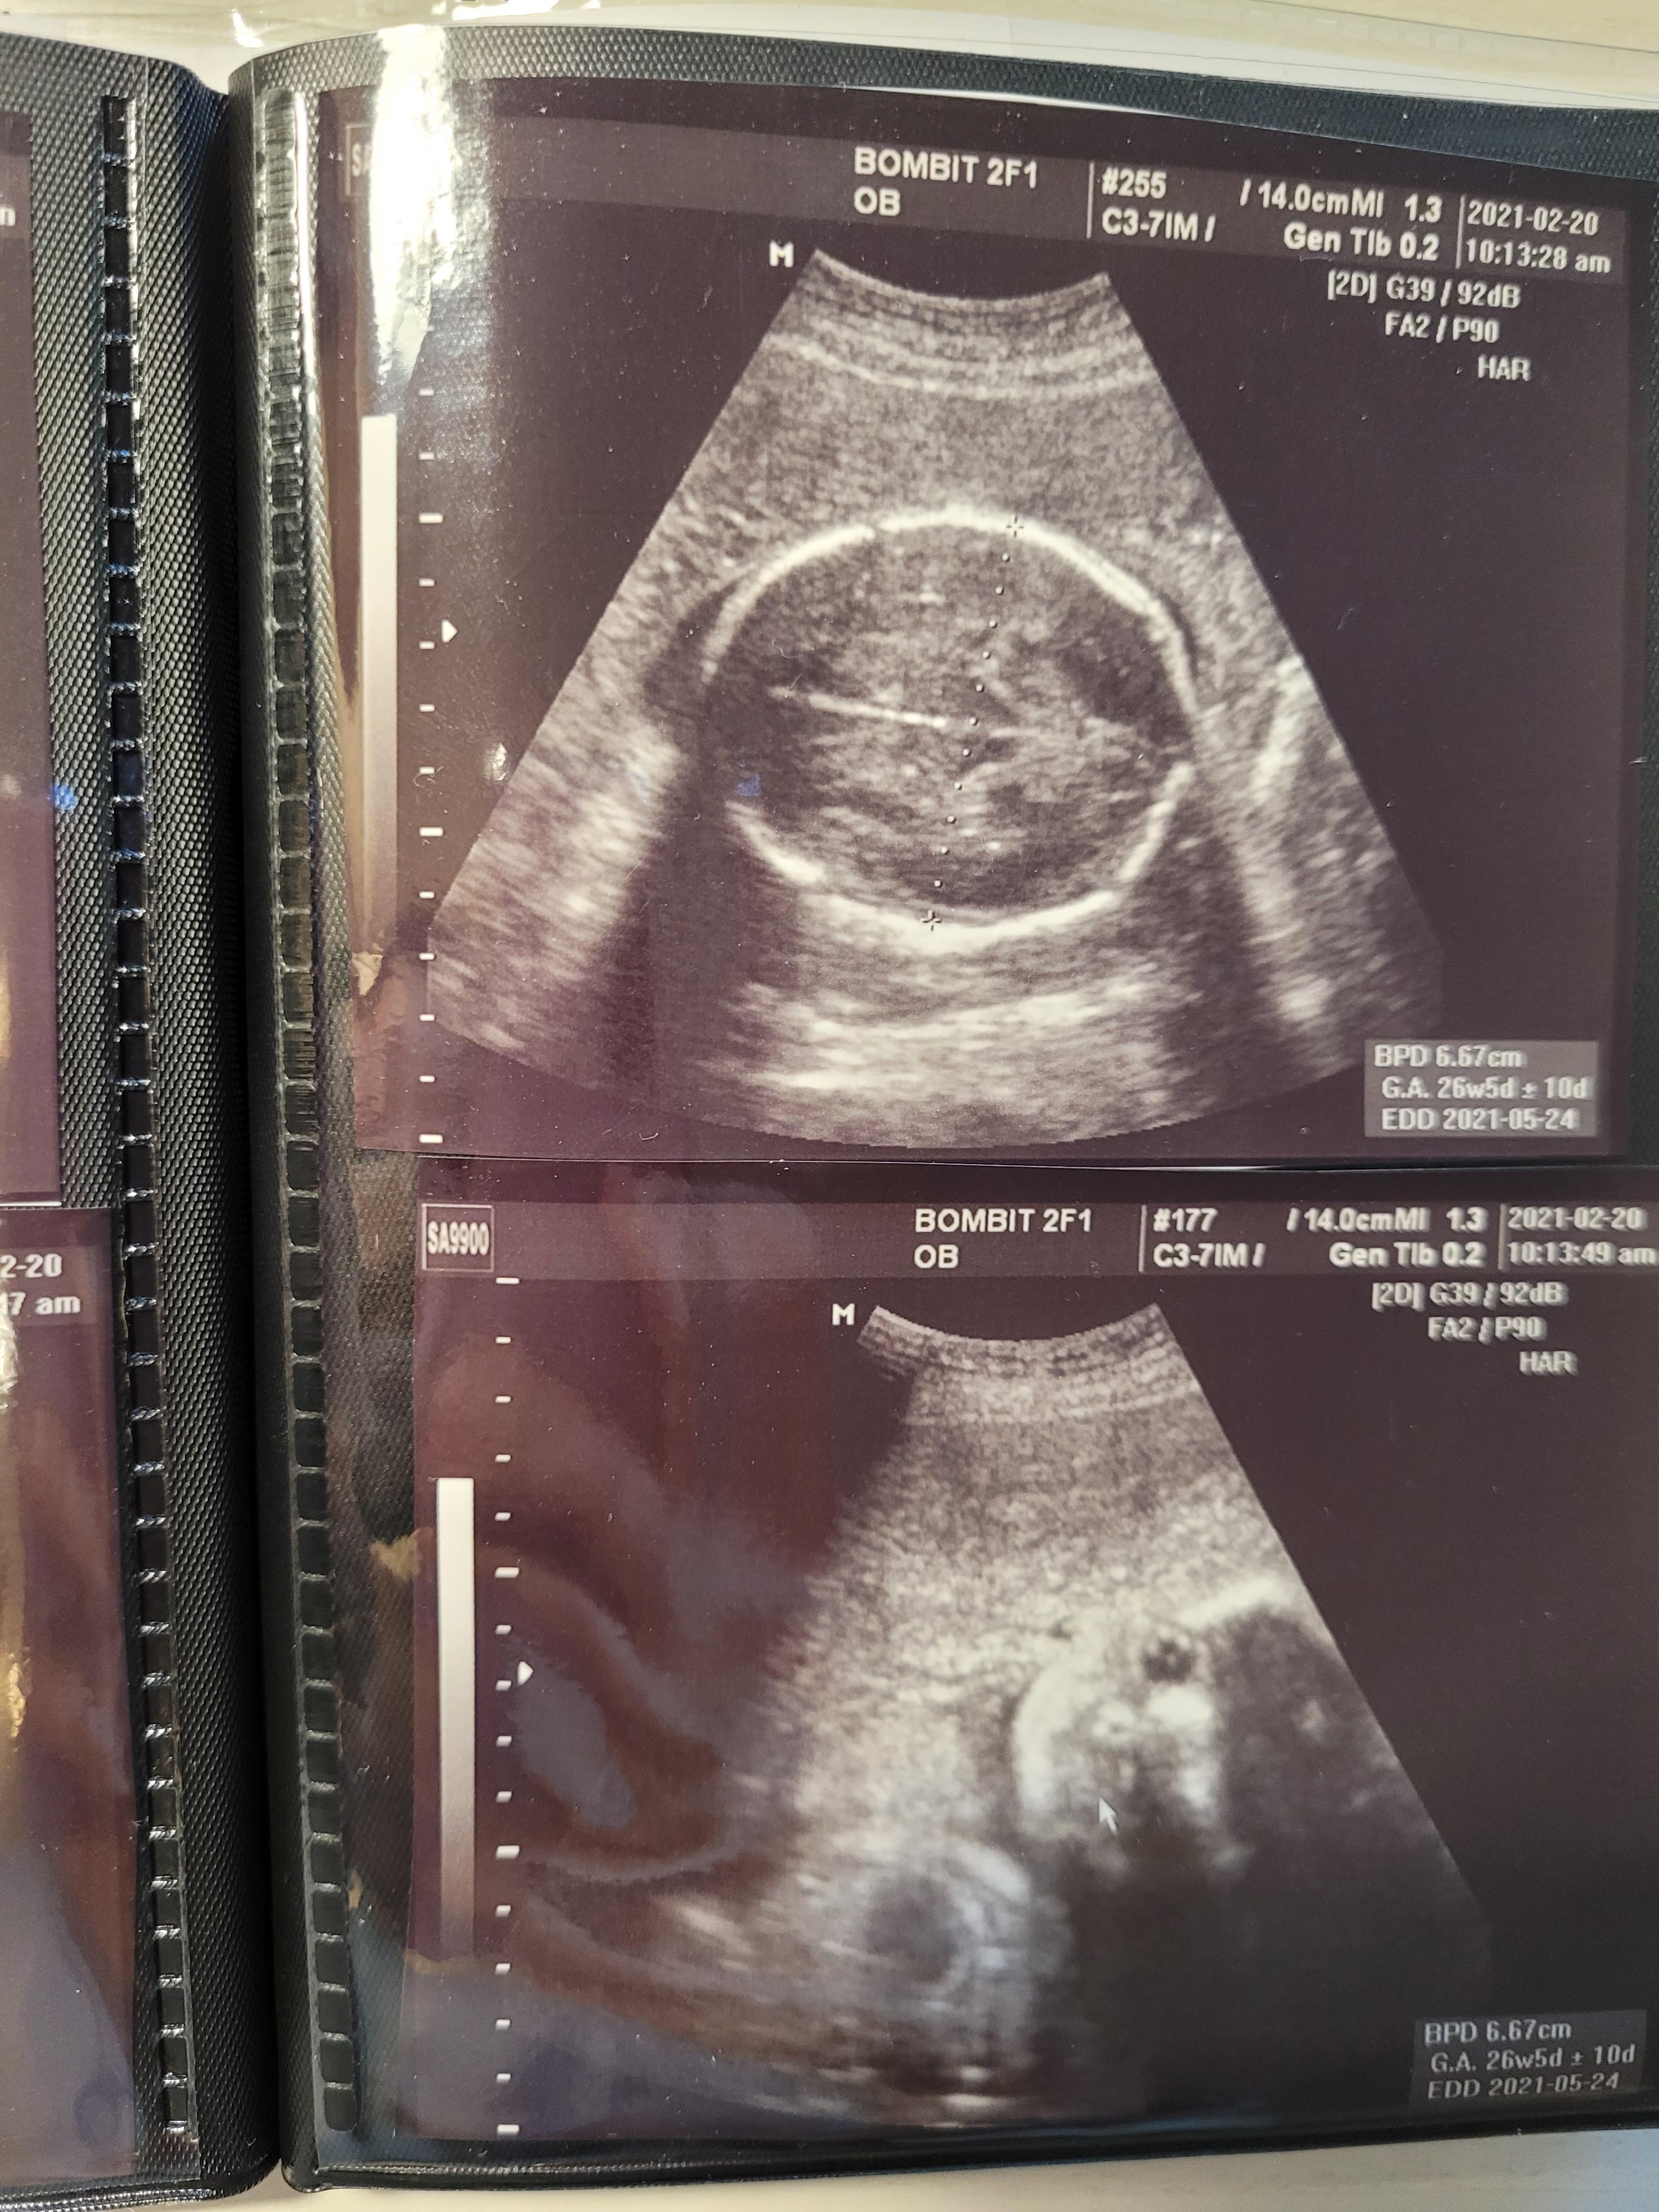

24주 초음파사진 / 24주 봄빛병원 정기검진

24주인데 2주나 앞서가는 우리 행복이..

머리둘레, 배둘레 다 체크하고 쑥쑥 잘 있는거 확인했어요.

아기는 900g정도되고, 양수도 넉넉하고 잘 있더라구요..^^